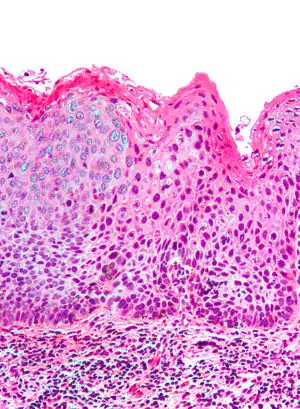

| Micrograph of (classic) vulvar intraepithelial neoplasia III. H&E stain. | |

Micrograph of vulvar intraepithelial neoplasia III. H&E stain.